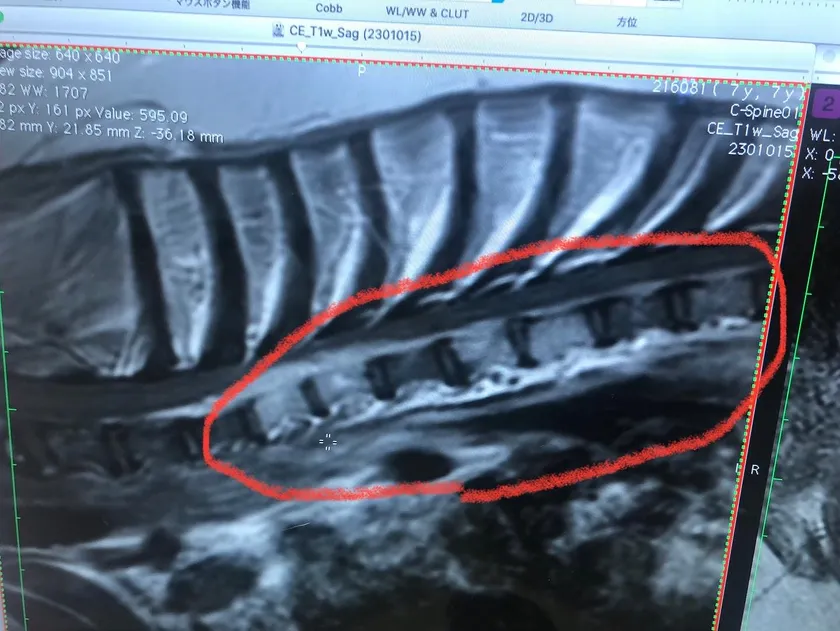

(2)

※腫瘍部を拡大して画像です。縦の白い柱が、腫瘍に侵されてしまった骨です。

左側、白い骨の上部に細長い雲の様に見える物も腫瘍です。

MRI検査で、頚椎6番の骨が腫瘍に侵されてしまい、骨に穴が空き、そこから腫瘍があふれ出てしまったため、神経を圧追し神経麻痺を引き起こしていました。

(3)

※骨に穴が開いているのが確認できます